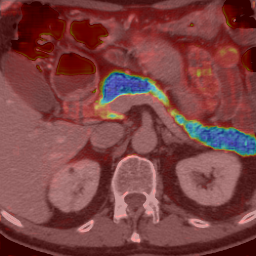

Expectation-Maximization Regularized DeepLearning for Weakly Supervised Tumor Segmentatio... https://t.co/Hvu6p1D66X